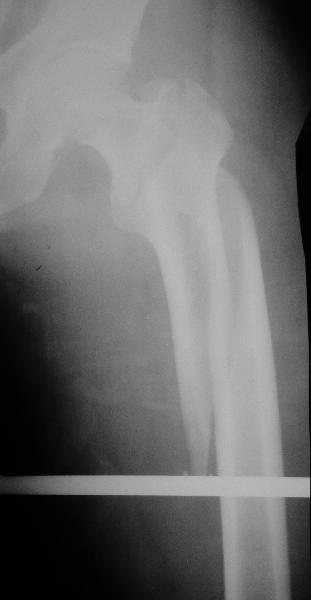

Дорогие коллеги,Как правильно определить такой перелом по классификации AO?

Как два отдельных или есть один соответствующий код? Фиксировать-то оба можно одним фиксатором...

Как раз недавно у меня был примерный случай: больному 36 лет, поступил ночью, травма в результате мотоциклетной аварии, кроме чрезвертельного и спирального перелома левого бедра имеется переломы костей предплечья с этой же стороны. Скелетное вытяжение, а на следующий день больной про оперирован на ортопедическом столе с дистракцией. Чтобы не расколоть чрезвертельный перелом провели временную спицу ближе к переднему кортексу, из малого разреза костодержатель для репозиции, а фиксацию провели антиградным штифтом. Этапы операции на снимках.

Да, сейчас это и у нас самый напрашивающийся выбор. Сделали гвоздем ChM, картинки в приложении.